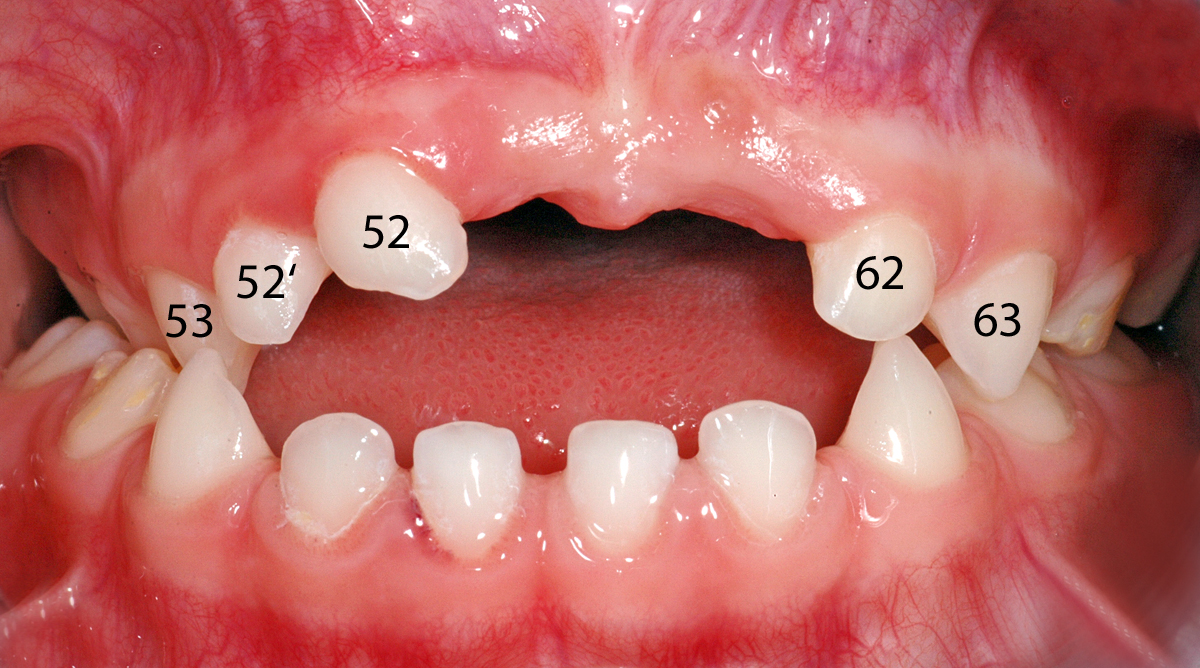

Anbei ein Fall einer 4½ Jahre alten Patientin, die Befunde in folgenden Bereichen aufzeigt: Unfallfolge mit Zahnverlust ( Punkt 1), überzählige Zähne (Punkte 2 und 3), Zahnstellungsabweichungen (Punkte 4 und 5).

1. Vorzeitiger Verlust von zwei oberen mittleren Milch-Schneidezähnen infolge eines Sturzes (der rechte, 51, wurde direkt nach dem Sturz entfernt, der linke, 61, musste etwa 6 Monate danach entfernt werden, da sich im Knochen an der Wurzel eine Entzündung gebildet hatte). Beide Zähne sind auf dem klinischen Bild schon nicht mehr zu sehen. Die Entzündung im Knochen und die vorzeitige Auflösung der Wurzel des Zahnes 61 sind auf dem Röntgenbild 1 mit schwarzen Pfeilen markiert.

2. Überzähliger seitlicher Milch-Schneidezahn rechts (52'); siehe dazu auch den Beitrag zu überzähligen Zähnen.

Klinisches Bild

Ansicht von vorne. Darauf sind die Zahnstellungsabweichungen und der überzählige Zahn zu sehen. In den weiteren Bildern sind die Befunde markiert.

Ansicht von vorne, Zähne nummeriert